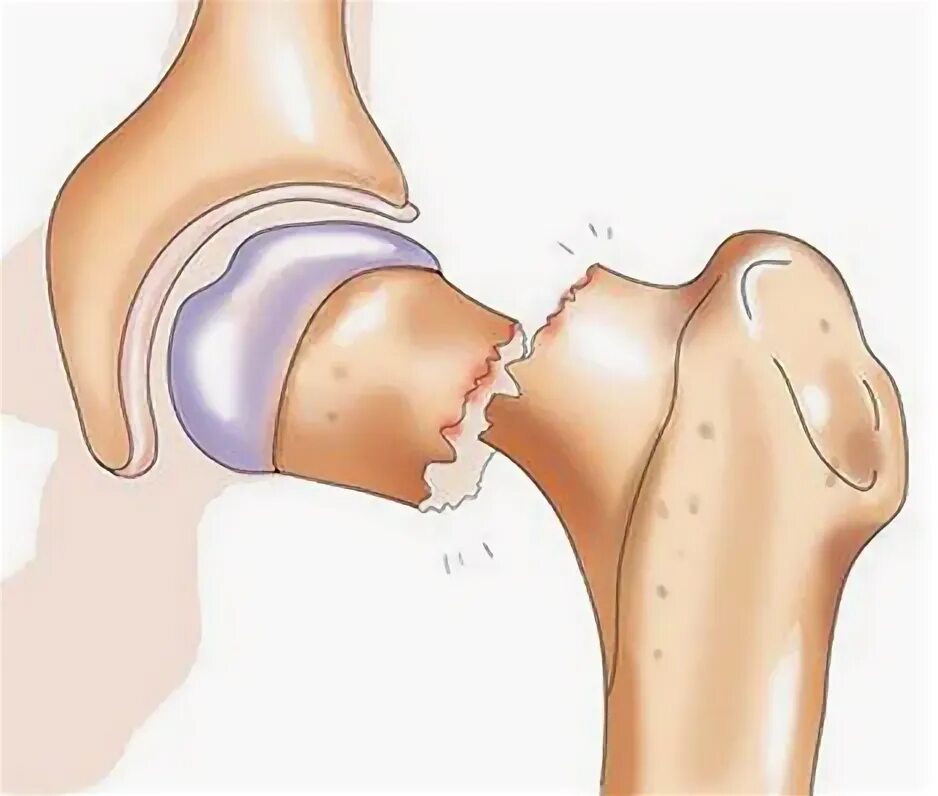

Перелом шейки бедра мкб 10 у взрослых